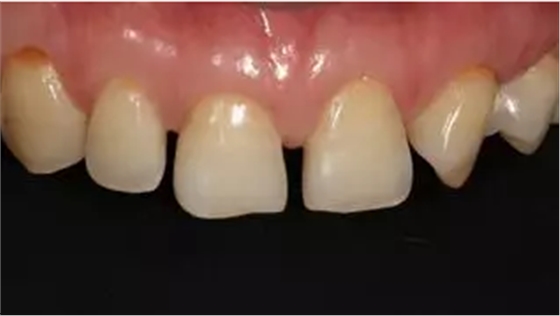

術(shù)前上前牙正面照

術(shù)前上前牙右側(cè)面照

術(shù)前上前牙左側(cè)面照

口腔衛(wèi)生尚可,牙齦正常。11,12,21,23 牙體完整,散在間隙,13、24、33、34 頸部楔形缺損,探診無明顯不適,叩(-),無明顯松動(dòng)。冷熱刺激無明顯不適。22 缺失。上下牙咬合穩(wěn)定,覆 覆蓋正常。